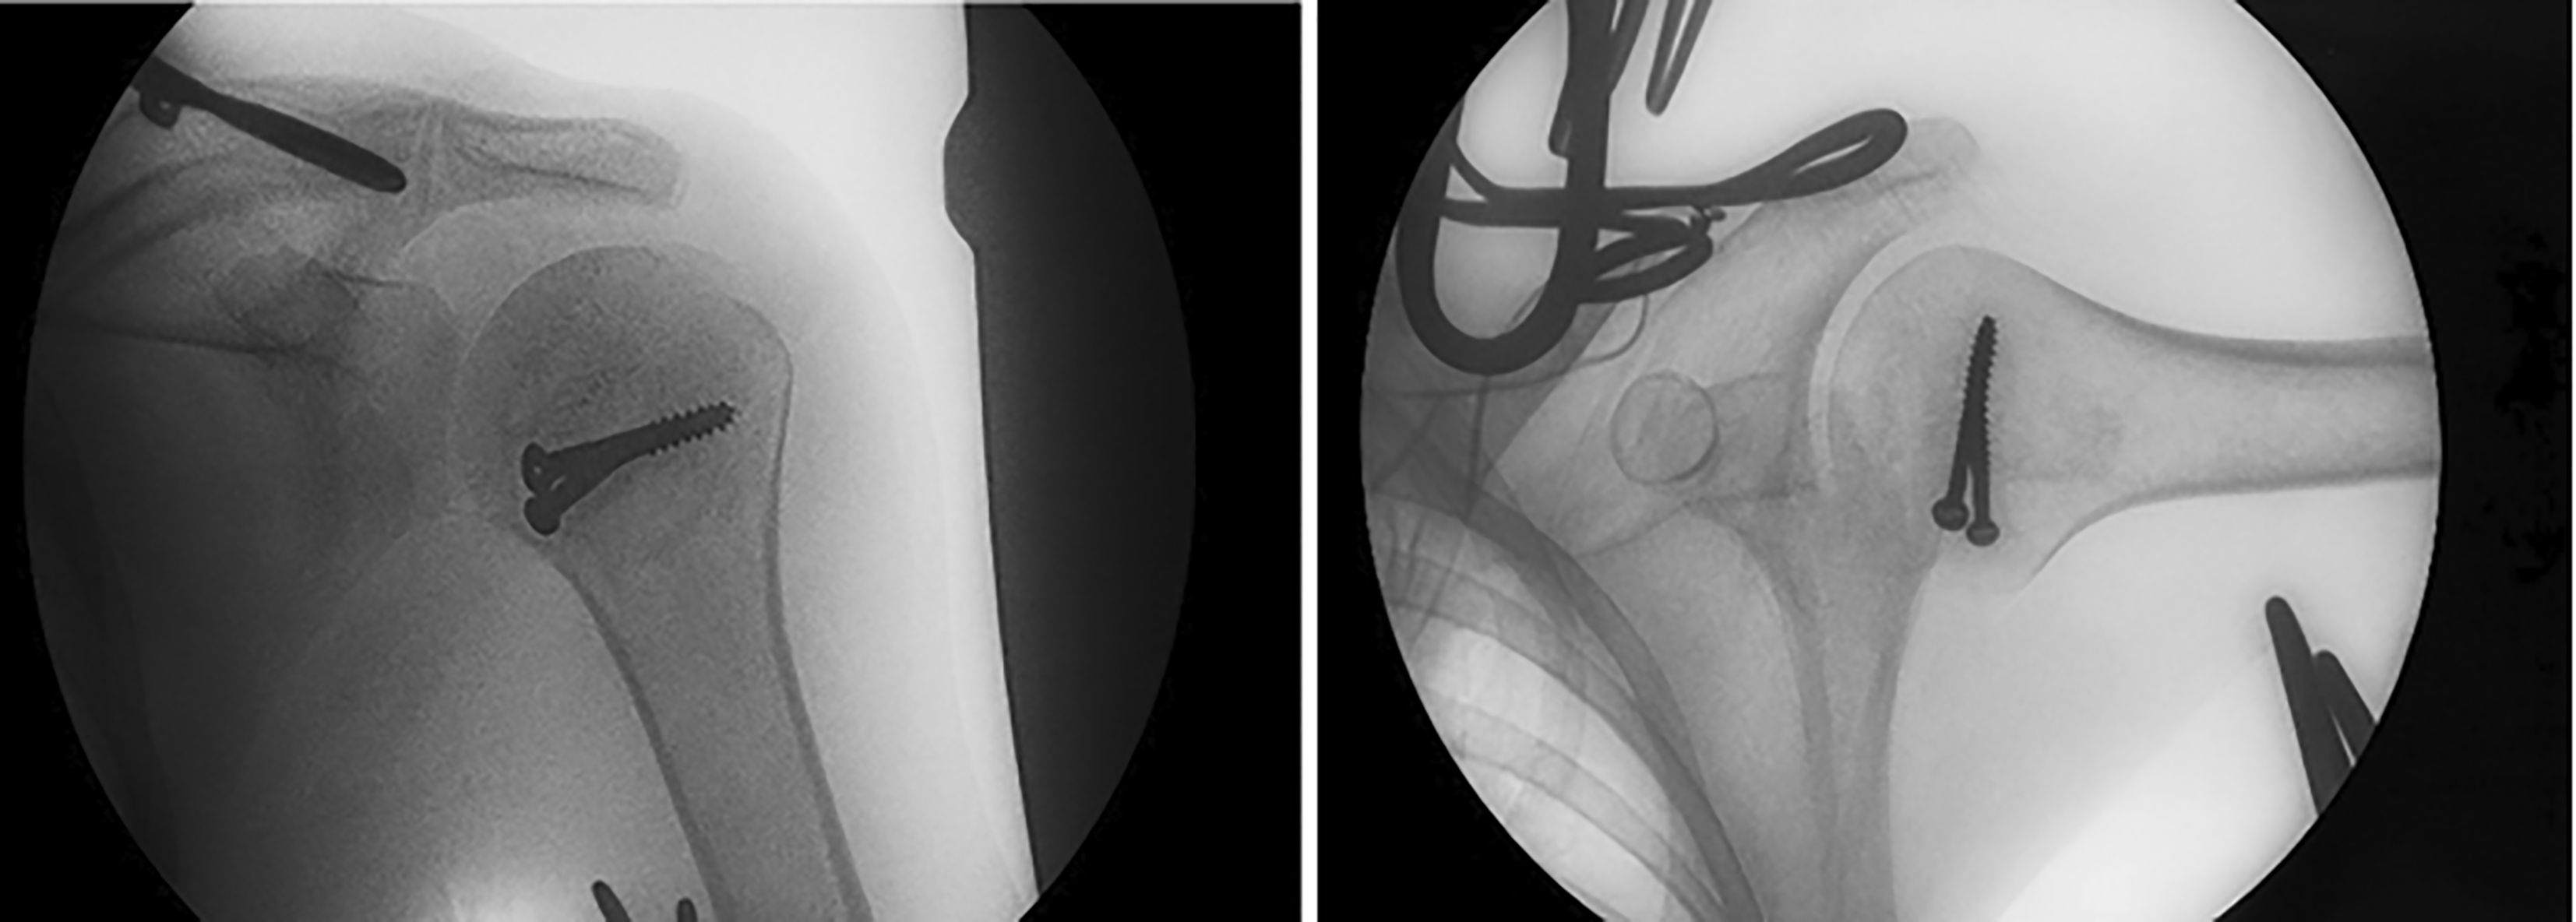

The management plan involved surgical reduction of this dislocation using the Modified McLaughlin Procedure. The patient was admitted to the operative room in Fallujah Teaching Hospital to undergo the surgical procedure using the deltopectoral approach to reduce the dislocation by the open method with transfer of the subscapularis with its lesser tuberosity to the defect (Reverse Hillsach) on the anterior part of the Humeral Head ( Figure 3).

Postoperatively, the patient wore a Gunslinger sling for 4 weeks, followed by exercise. The postoperative radiograph is shown in ( Figure 4).

The management plan involved surgical reduction of this dislocation using the Modified McLaughlin procedure. The patient was admitted to the operative room at Fallujah Teaching Hospital to undergo the surgical procedure using the deltopectoral approach to reduce the dislocation by the open method with transfer of the subscapularis with its lesser tuberosity to the defect (Reverse Hillsach) on the anterior part of the Humeral Head with Bone Graft ( Figure 7).

Postoperatively, the patient wore a Gunslinger sling for one month followed by exercise. The postoperative radiograph is shown in ( Figure 8).

Under General Anesthesia, closed reduction successfully reduced the head with external rotation of the Humeral Head with a snap. Examination of shoulder joint movement under anesthesia revealed a full range of movements ( Figure 11).